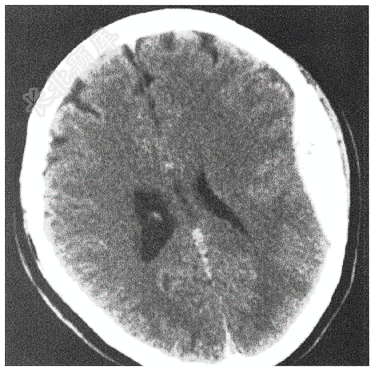

- 单项选择题男性,55岁,头都摔伤3小时,头颅CT平扫结果如下图,诊断为( )

A、右侧硬膜外血肿

B、高血压脑出血

C、左侧硬膜外血肿

D、右侧硬膜下血肿

E、左侧硬膜下血肿